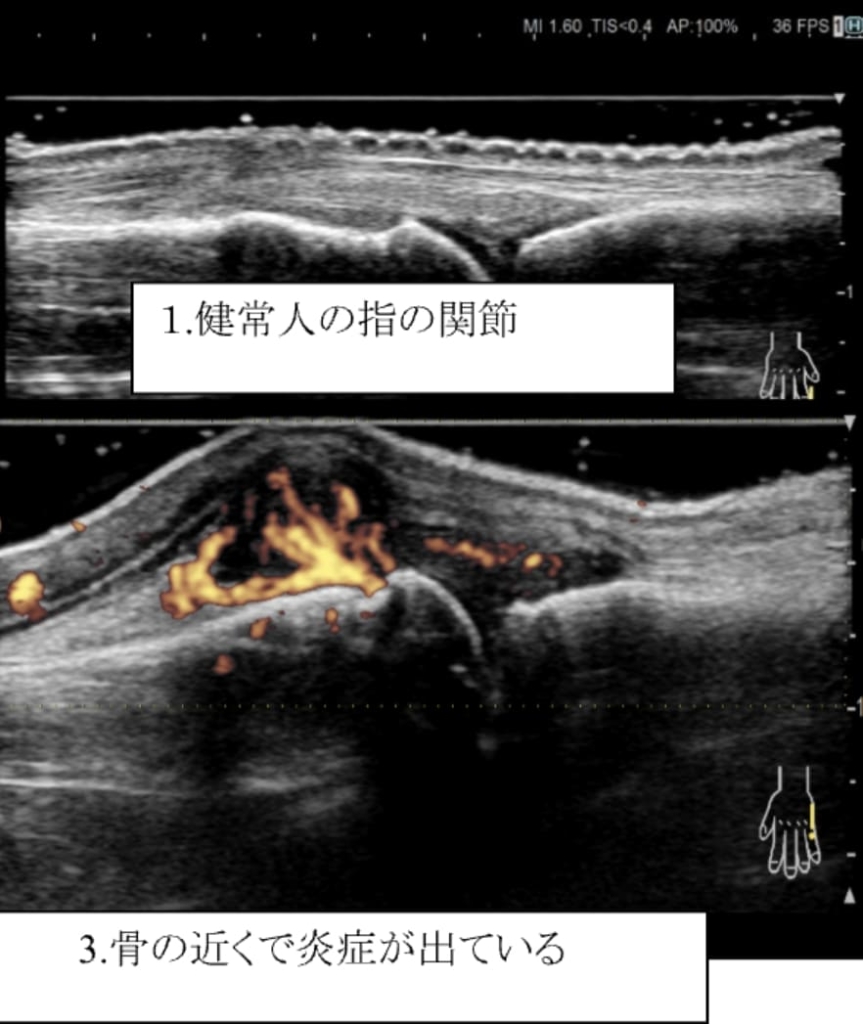

関節リウマチは、関節滑膜が炎症を起こすと厚みを持ち(滑膜肥厚)、滑膜内には異常な血流として示されます(滑膜炎)。これらを「関節エコーガイドライン」に沿って評価し治療に反映しています。

炎症が続くとどうなるの?

同じ関節で炎症が続くと、骨破壊(骨びらん)が起き関節の変形がみられます。また、腱や靭帯で炎症が続くと切れてしまう恐れがあります。